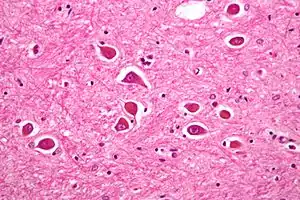

![]() Уражені астроцити при хворобі Альцгеймера, їх можна також спостерігати й при печінковій енцефалопатії Уражені астроцити при хворобі Альцгеймера, їх можна також спостерігати й при печінковій енцефалопатії | |

Аміак є одним з головних факторів патогенезу печінкової енцефалопатії. Через недостатній метаболізм у печінці, кров у кишковому тракті насичується аміаком, звідки вона потім надходить у системний кровоток. Аміак через це потрапляє в головний мозок через гематоенцефалічний бар'єр і поглинається астроцитами. Астроцити метаболізують поглинений аміак до глутаміну, який спричинює осмотичну дію на об'єм астроцитів. Внаслідок цього виникає набряк астроцитів, який призводить до набряку мозку, вважається основною причиною печінкової енцефалопатії.